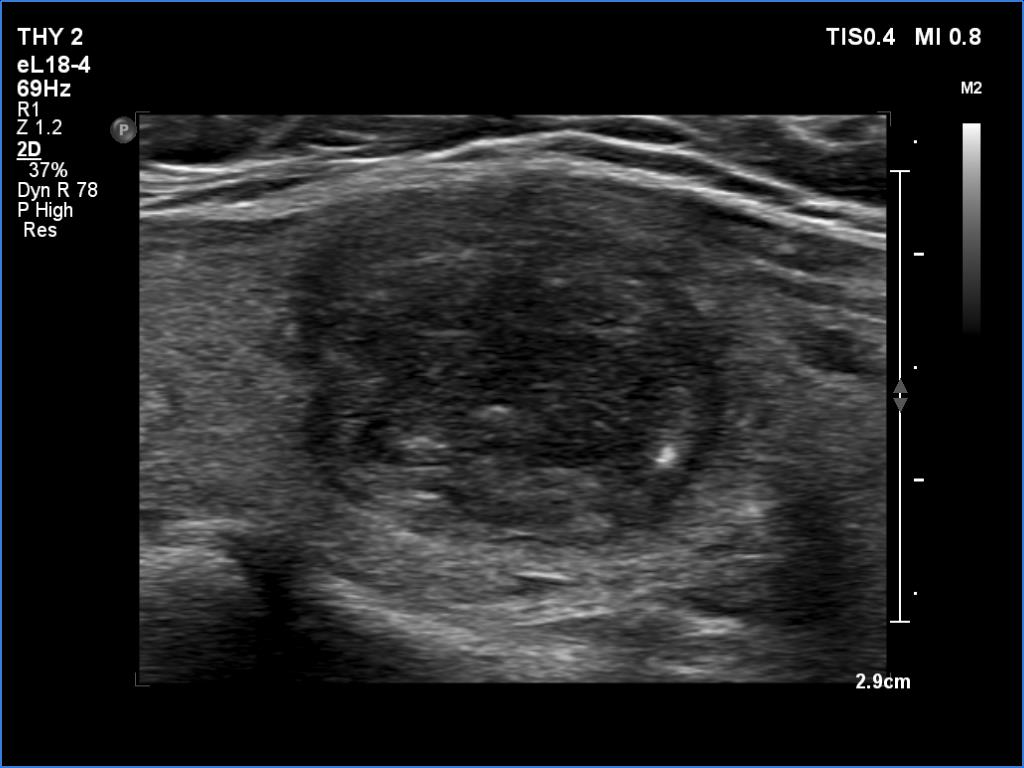

Ultrasonography revealed an echonormal thyroid. There was dominantly moderately hypoechoic nodule in the right lobe. Some parts of the lesion were deeply hypoechoic, and a few small cystic chambers were also within. The nodule presented with irregular shape and borders and had intranodular echogenic figures, primarily granules.

It is ambiguous how to interpret the echogenic figures. Although the presence of irregular shape and borders increases the likelihood that the echogenic granules are indeed microcalcifications, comet-tail artifacts must be also considered.

It is worth comparing the images recorded by using different settings. By using harmonization, we lose the details of very hypoechoic areas. Essentially, the latter seem to be anechoic.